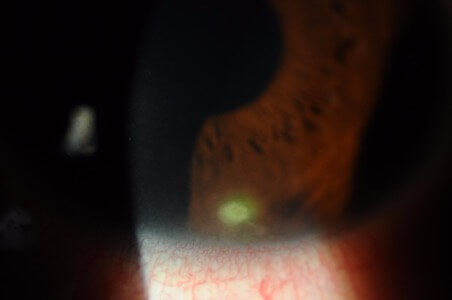

角膜浸潤

照片由香港理工大學眼科視光學院提供

巨乳突結膜炎 或者 異物相關乳突結膜炎

照片由香港理工大學眼科視光學院提供